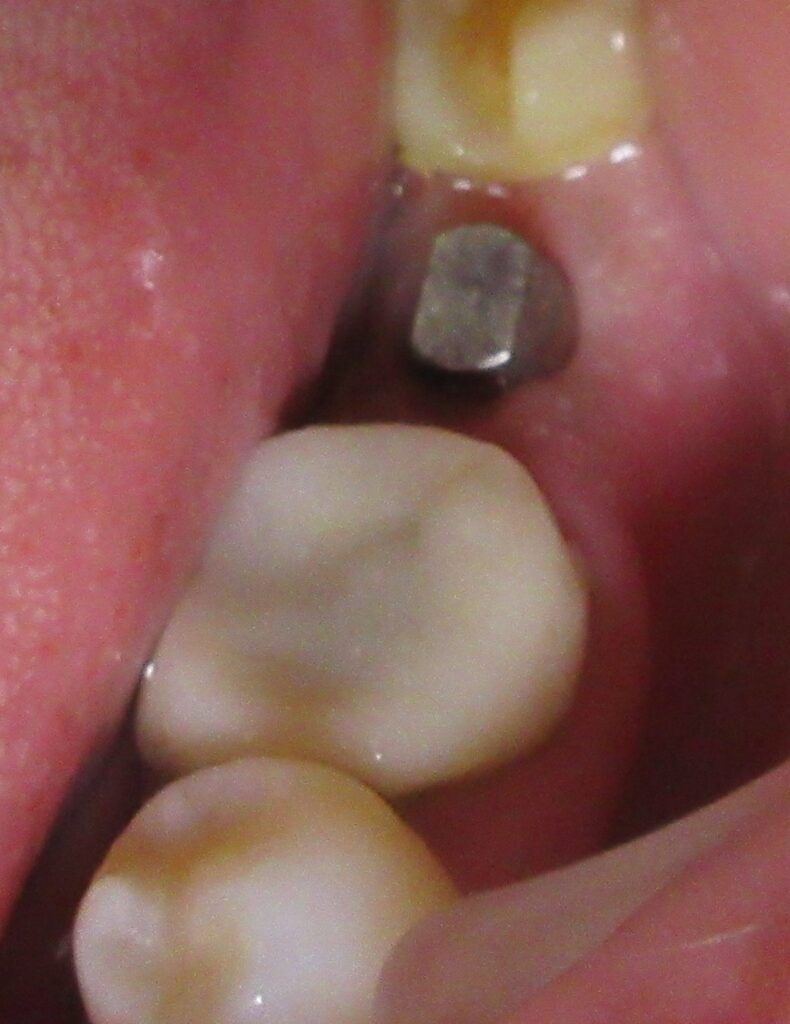

しっかりとインプラント埋め込まれた後は、動揺がないか、噛んだ時に当たらないかなどを確認して、最後にパノラマ写真を撮影して今回のオペは終了となりました。

その後は定期的にお掃除や検診に通院していただき、約3か月経過した後に、きれいな差し歯を入れていきます。